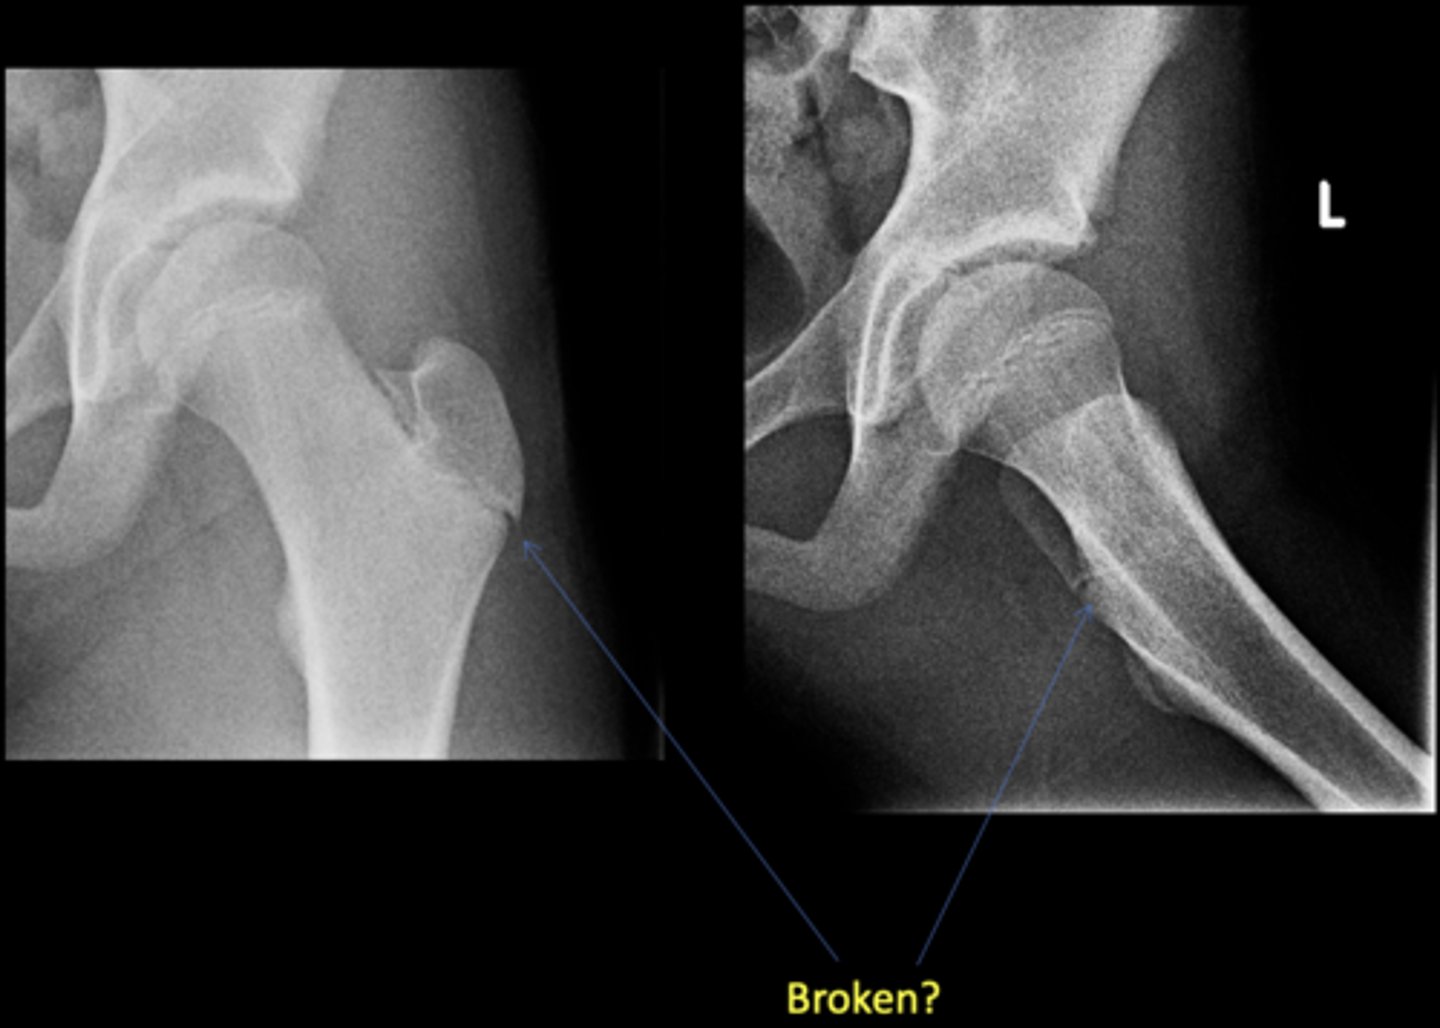

No - growth plate in a child

Broken?

<p>Broken?</p>

21

New cards

22

AP hip

View on left?

<p>View on left?</p>

23

Frog-leg hip

View on right?

<p>View on right?</p>